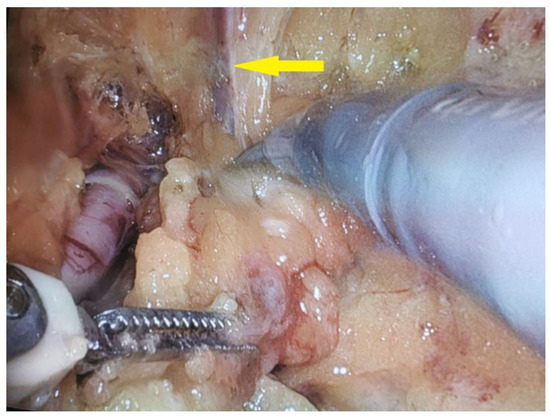

2.4. Salvage Surgical Intervention